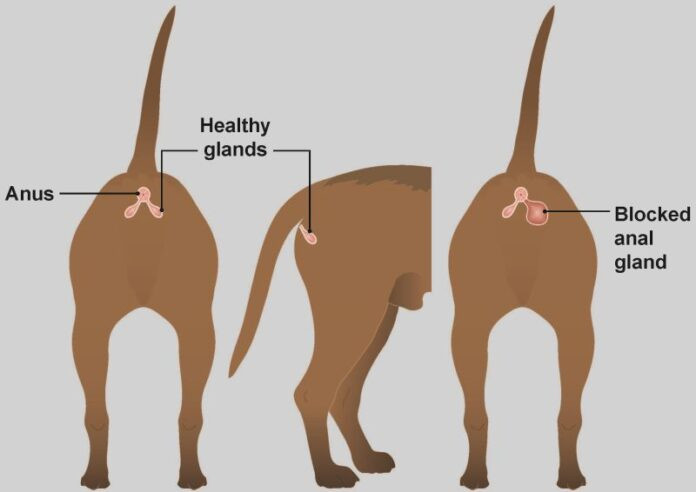

Causes courantes de mauvaises odeurs

Causes courantes de mauvaises odeurs

Causes courantes de mauvaises odeurs